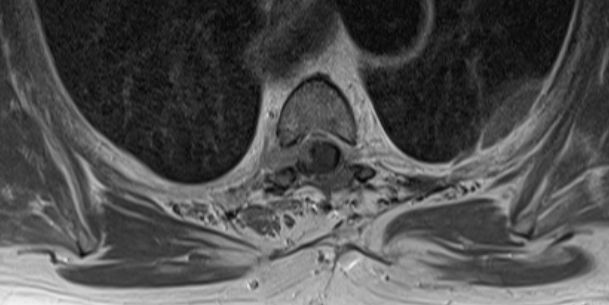

| Rückenmark |

76-jährige Frau mit Rezidiv eines Rückenmarks-Meningeoms. Erstmanifestation vor 17 Jahren. Rezidive von 12, 6 und 3 Jahren jeweils operativ beherrscht. Seit einem Jahr erneut Schmerzen zwischen den Schulterblättern und Druckgefühl im Thoraxbereich. Reduzierter AZ und adipöser EZ. KHK, VHF, Hypertonie, Hypothyreose. Auf Rollator angewiesen. Zunehmende Gangunsicherheit und Kribbeln in den Beinen. Klopfschmerz im Bereich von BWK2-5 stark auslösbar. Die Schmerzen strahlen zeitweise in die Schulterblätter aus. | ![]() | |||||

![]() |

![]() | ||||||